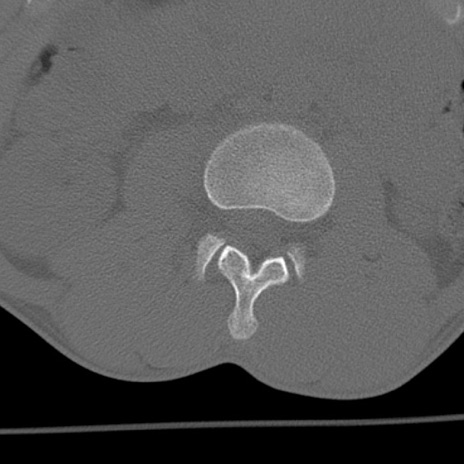

症例3 腰椎CT(横断像)

腰椎CT